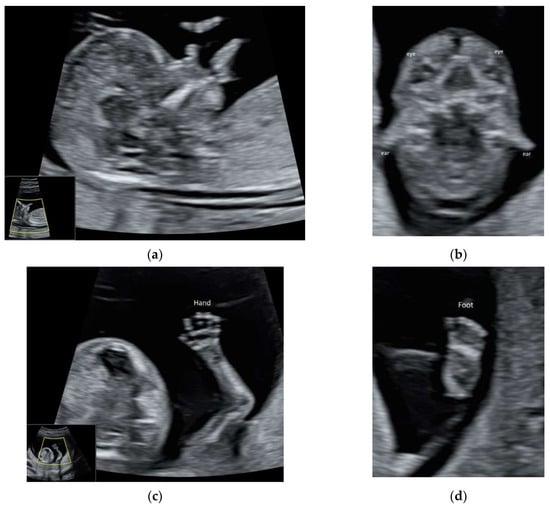

5.3. 3D Ultrasound Examination of Face, Limbs, and Other Structures